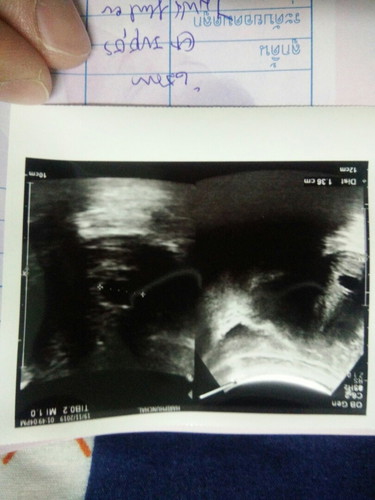

คุณแม่ท่านไหนเคยมีอาการแบบนี้บ้างค่ะ อายุครรภ์ประมาณ6wมีเลือดสีออกน้ำตาลๆๆดำๆออกเหมือนประจำเดือนมาติดต่อกันสามวันแล้วไปหาหมอชีดยากันแท้งให้แล้วอยากทราบว่าเป็นอาการแบบไหนค่ะกังวลมากเลยค่ะตอนนี้แนะนำหน่อยค่ะ